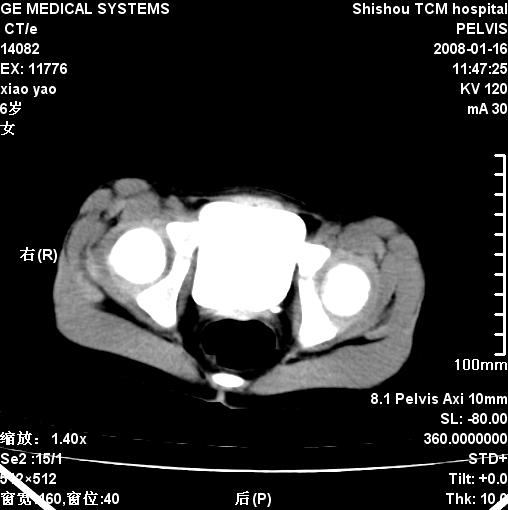

女,6岁,因腹痛做b超检查发现囊性包块.

【鉴别诊断】

瘤样病变:

1、卵巢或输卵管系膜单纯囊肿,囊肿的部位位于盆腔,可以是来自卵巢,囊肿一般较圆,除非破裂。

2、输卵管积水,形态不规则,下部较大,上部形态分叶,积液一般越远侧越扩张,先天性可以不确定。

3、肠系膜淋巴管囊肿,形态可以不规则。

4、肠重复畸形,与肠管分界不清,本例也是这样,见部分临近肠壁增厚。

肿瘤

1、卵巢囊性不典型无脂肪畸胎瘤

2、囊腺瘤

【诊断】

盆腔囊性占位,良性,来源难定。